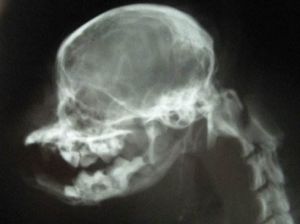

復位

下頜骨脫位復位以Barton繃帶固定下頜骨於復位後的位置.患者至少在6周內應避免大張口.當患者要打哈欠時,應以拳抵住頦部,以防止大張口.如這種脫位不是第一次發生,應請口腔頜面外科醫師會診.外科手術為拉緊(縮短)圍繞顳頜關節周圍的韌帶或修整下頜關節結節(使將來能較容易地自動復位).